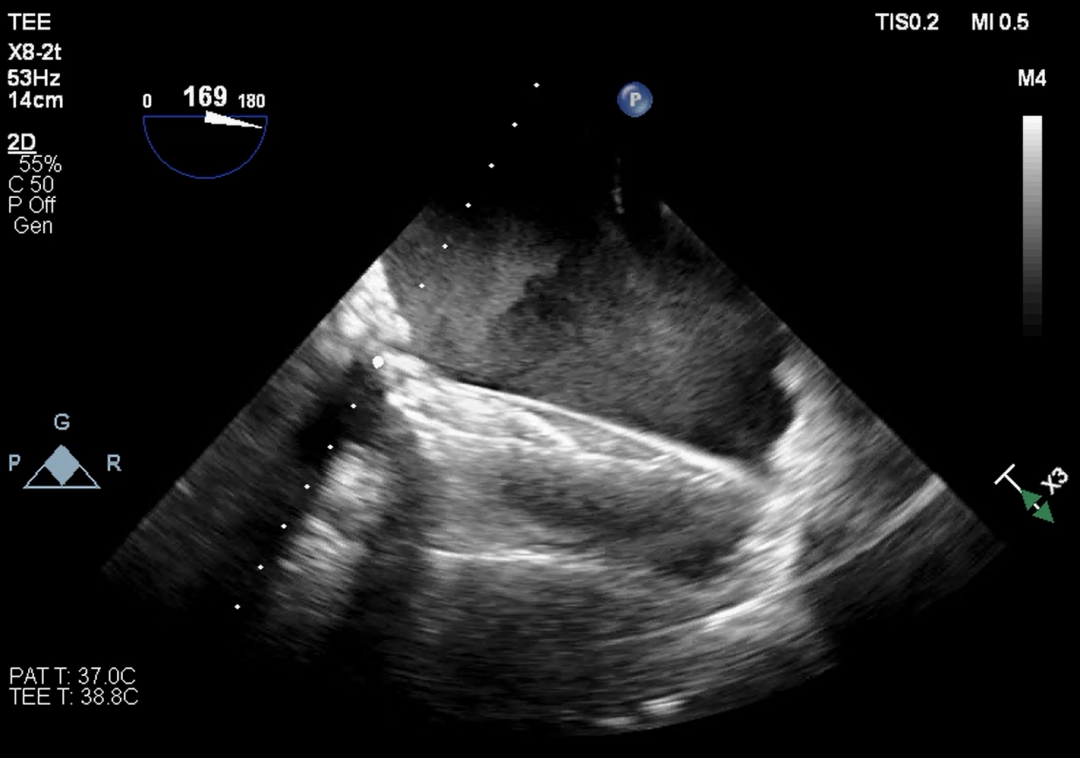

超声提示

无论开展任何瓣位的瓣中瓣手术前,都应先明确原外科生物瓣的类型和型号,不同类型的外科生物瓣都具有不一样的透视下特征,如果透视性差的情况下,术中需要结合TEE协助定位。同样,原外科生物瓣的尺寸也对介入瓣尺寸的选择至关重要。

本例患者15年前因三尖瓣增厚伴重度反流,接受31#三尖瓣生物瓣置换。该类型的外科生物瓣在影像下透视性差,术中难以清晰捕捉其形态和位置。同时,其右心室狭小,留给介入瓣操作的空间有限,使得本次手术难度升级。宁波市第一医院心外科励峰主任团队凭借丰富的瓣膜外科手术经验,成功经右房途径TTViV植入一枚29#的J-Valve瓣膜。J-Valve经心尖介入瓣膜系统,在治疗生物瓣衰败的改为患者中行瓣中瓣植入术可以取得良好的临床效果。其独特的定位件设计,能够准确牢固地锚定在原生物瓣的瓣脚上,降低瓣膜移位的发生率。术后,患者三尖瓣跨瓣压差、反流及右房压均明显改善,即刻获益。